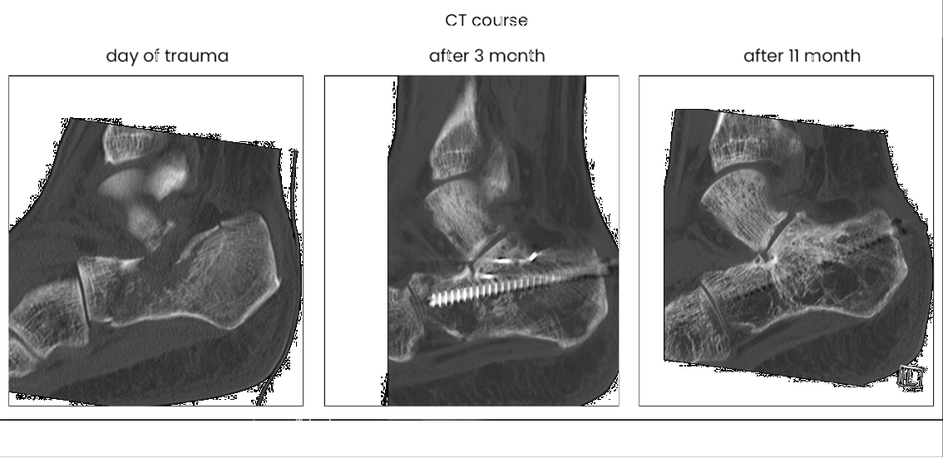

case 17BD, 47 years old, male, fall during work, 2 meters, "comminuted fracture", surgery after 2 days